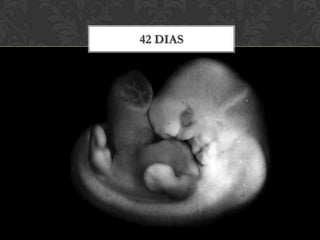

42 dias